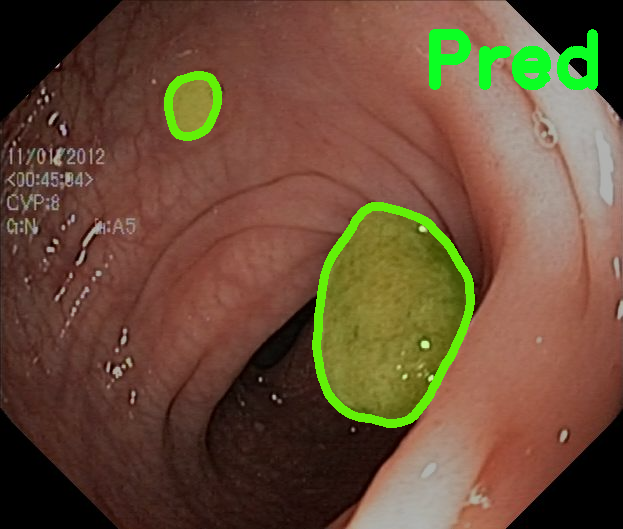

TransFuse is evaluated on both 2D and 3D datasets to demonstrate the effectiveness. As different medical image segmentation tasks serve different diagnosis or operative purposes, we follow the commonly used evaluation metrics for each of the segmentation tasks to quantitatively analyze the results. Selected visualization results of TransFuse-S are shown in Fig. 2.

Results of Polyp Segmentation. We first evaluate the performance of our proposed method on polyp segmentation against a variety of SOTA methods, in terms of mean Dice (mDice) and mean Intersection-Over-Union (mIoU). As in Tab. 3, our TransFuse-S/L outperform CNN-based SOTA methods by a large margin. Specifically, TransFuse-S achieves 5.2% average mDice improvement on the unseen datasets (ColonDB, EndoSene and ETIS). Comparing to other transformer-based methods, TransFuse-L* also shows superior learning ability on Kvasir and ClinicDB, observing an increase of 1.3% in mIoU compared to TransUnet. Besides, the efficiency in terms of the number of parameters as well as inference speed is evaluated on an RTX2080Ti with Xeon(R) Gold 5218 CPU. Comparing to prior CNN-based arts, TransFuse-S achieves the best performance while using only 26.3M parameters, about 20% reduction with respect to HarDNet-MSEG (33.3M) and PraNet (32.5M). Moreover, TransFuse-S is able to run at 98.7 FPS, much faster than HarDNet-MSEG (85.3 FPS) and PraNet (63.4 FPS), thanks to our proposed parallel-in-branch design. Similarly, TransFuse-L* not only achieves the best results compared to other Transformer-based methods, but also runs at 45.3 FPS, about 12% faster than TransUnet.